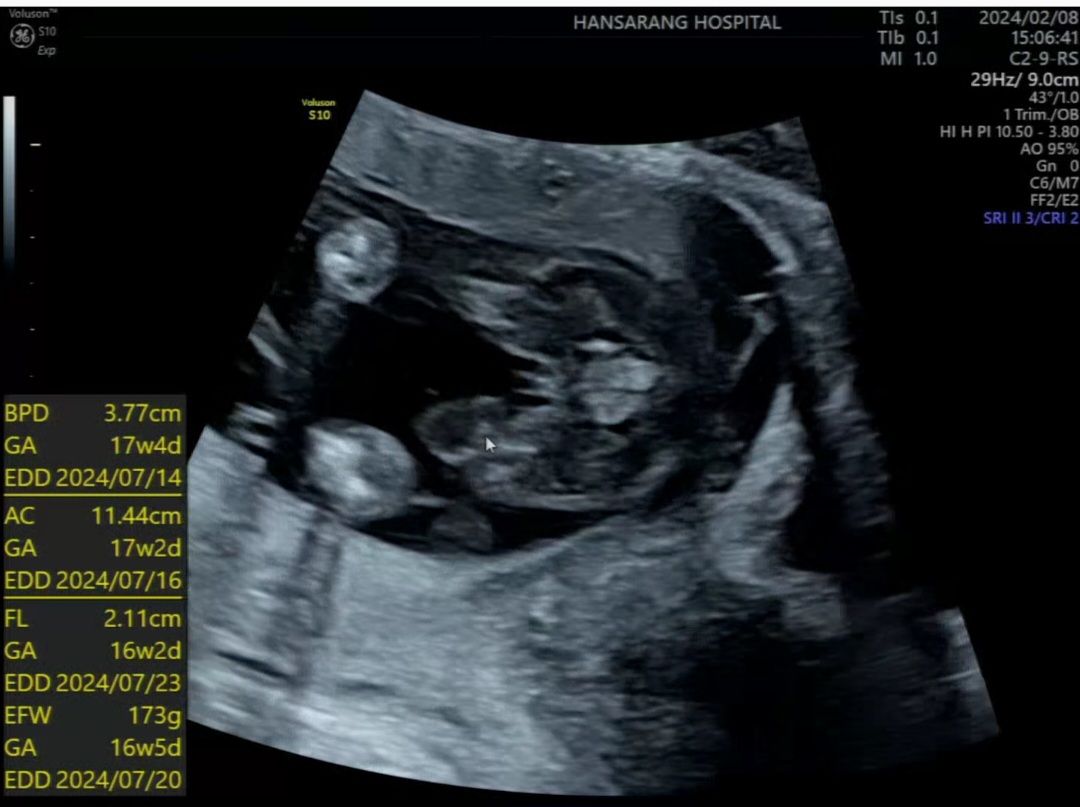

16주 초음파... 어려워요 ㅠㅠ

명절 앞두고 잠 안오시는 고수님들 도와주세요 ㅠㅠ 16주인데 선생님도 긴가민가 하시더라구요 ㅠ